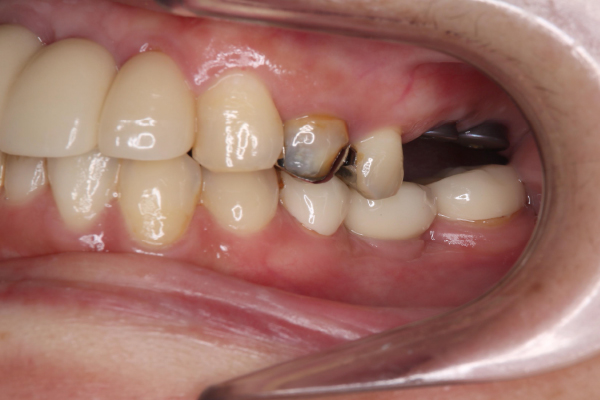

Case.02

インプラントの症例 インプラントの症例

治療前〜治療後のレントゲン写真

患者様の要望奥歯にインプラント治療したい

治療期間4ヶ月

治療費用880,000円

治療内容左上奥歯に2本インプラント埋入

治療のリスクネジが緩む可能性あり